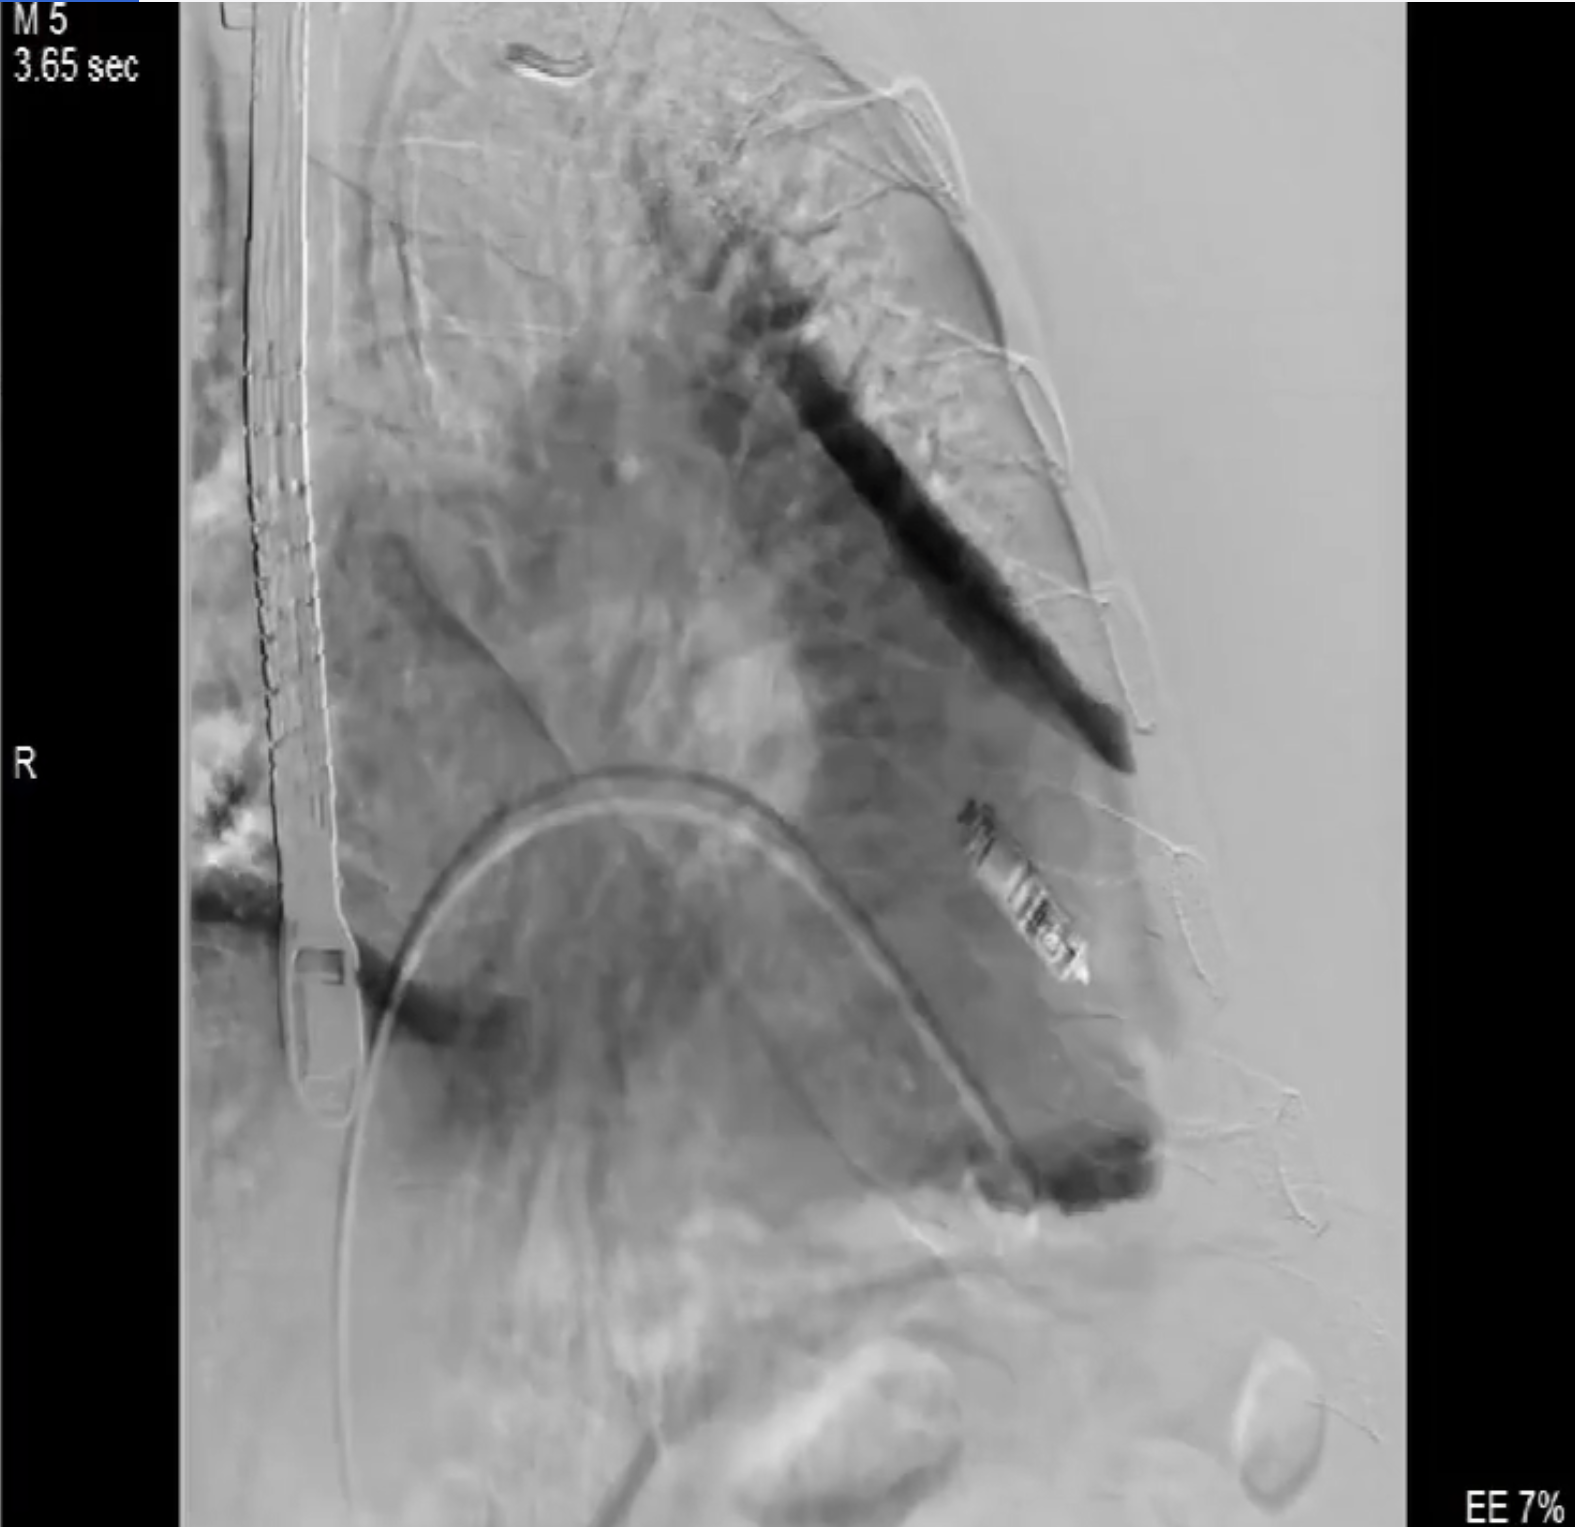

術(shù)中影像

術(shù)前DSA造影可見三尖瓣大量返流呈瀑布樣,右室偏間隔側(cè)可見無導(dǎo)線起搏器一枚。